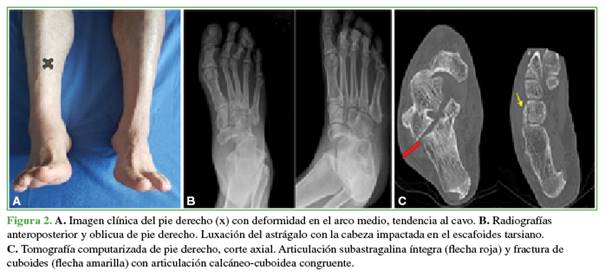

En el posoperatorio, se solicitaron radiografías de control, se administró analgesia, profilaxis antibiótica intravenosa durante 24 h y se indicó rehabilitación precoz a cargo de Fisiatría.

Al concluir el seguimiento a los 18 meses, el paciente tenía un pie estable, plantígrado, no doloroso y el puntaje de la American Orthopaedic Foot and Ankle Society era de 87. En la Figura 3, se muestra la consolidación completa de la artrodesis.